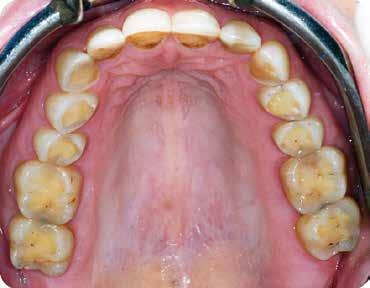

A páciens fogazata esztétikai megjelenésének és funkcionális működésének a lehető legtöbb, saját foganyag megtartása mellett történő helyreállítása (1. és 3. ábra).

A kezelés megtervezése során kifejezett jelentősége van annak, hogy jó kommunikáció legyen a páciens, a fogorvos és a fogtechnikus között. A páciens leendő fogazatának természetes megjelenését a kezelésben részt vevő team szakmai felkészültsége, gyakorlati tapasztalata és a kezelés sikerességének irányába történő elkötelezettsége biztosítja. A beavatkozások megkezdése előtt megtörtént a páciens anamnézisének a felvétele, valamint a klinikai kivizsgálását is elvégeztük. Ezt követően lenyomatokat készítettünk a kiindulási állapotról, majd a kiindulási helyzetet extra- és intraorális fotók segítségével is rögzítettük (13. a-c. ábra).